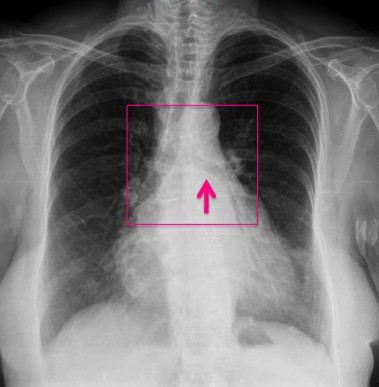

CASO: sospecha de neumonía.

Hallazgos:

- En un principio podríamos decir que existe un aumento de densidad retrocardiaco que podría ser compatible con condensación neumónica a dicho nivel, sin embargo estamos ante una placa poco inspirada, lo cual puede llevarnos a cometer errores diagnósticos.

- Se recomendó volver a realizar la radiografía, observar a continuación:

Ya no se observa el aumento de densidad retrocardiaco, la placa es normal.

INSPIRACIÓN: Una placa bien inspirada es aquella en la que se observar 6-7 arcos costales anteriores o 10-11 arcos costales posteriores. Lo contrario puede producir imágenes falsas de condensaciones o de seudocardiomegalia.